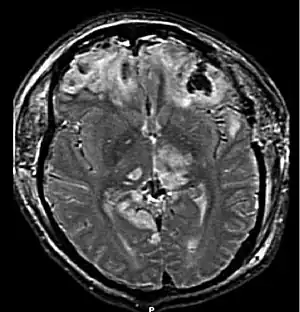

![]() | |

| MRI showing injury due to brain herniation | |